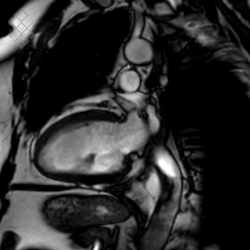

IRM Cardiaque morphologique